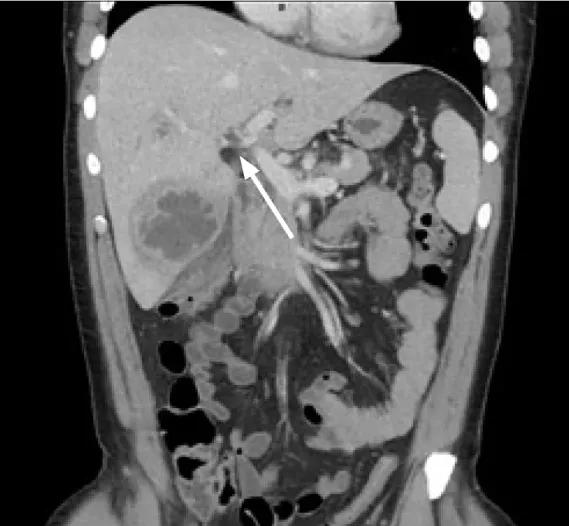

如此精壮的男子缘何无故发生肝脓肿?仔细一看,原来门静脉还有感染性血栓(图2)!

图2.门静脉感染性血栓